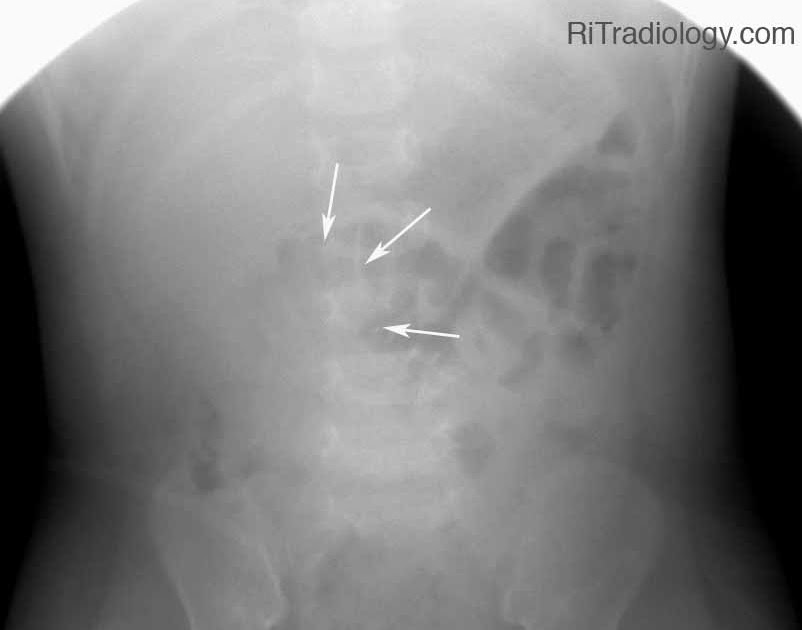

From radiologyinthai.blogspot.co.uk

RiT radiology Intussusception Reduction Intussusception Cat X Ray This finding along with the clinical signs suggests the presence of an intussusception. Causes include mechanical obstruction (e.g., foreign body, intussusception, mass). Survey radiographs may reveal area of obstruction, such as a tubular soft tissue mass, or gas highlighting area of intussusception. The intussusception was within the right lower abdomen, and in retrospect likely represents the soft tissue density on. Intussusception Cat X Ray.

Target Sign Intussusception X Ray Many plain radiographic signs of Intussusception Cat X Ray This finding along with the clinical signs suggests the presence of an intussusception. Luminal distention is greater than 2 times normal (4 to 5 times the width of a rib). Survey radiographs may reveal area of obstruction, such as a tubular soft tissue mass, or gas highlighting area of intussusception. The presenting signs in dogs and cats with intussusception are. Intussusception Cat X Ray.